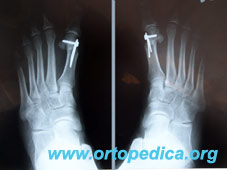

Рентгенограммы стоп после шеврон остеотомии